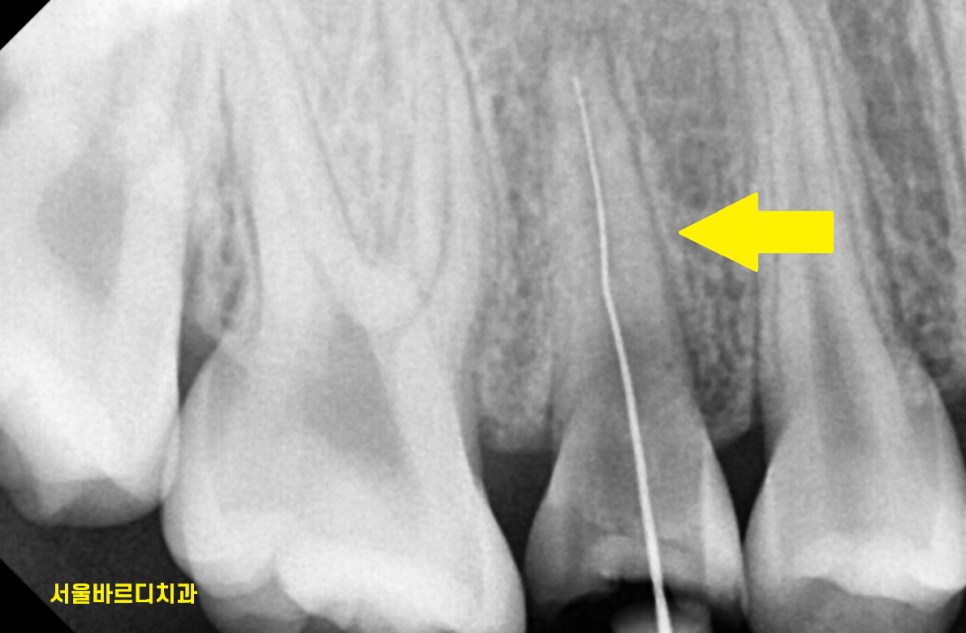

환자분은 x-ray를 찍어보았을 때

뿌리 끝에 염증이 없고

치아 흔들림이 없기에

살려볼 수 있었는데요.

치아가 뿌리쪽까지 부러지긴 했지만

절반 정도가 남아 있어서

신경치료 후 살려보기로 하였습니다.